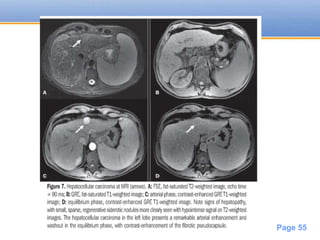

MRI

T1(variable)

T1 C+ (Gd)

Enhancement similar to CT

Rim enhancement may persist

T2 –Hyperintense

Post SPIO (Iron oxide) - increases sensitivity

in diagnosing small HCC’s

• #31 This is on account of the supply to HCCs being from the hepatic artery rather than portal vein iso or hyperintense(T1) Early arterial enhancement and rapid washout becoming hypointense to the liver Superparamagnetic iron oxide based MRI

• #32 A 3-cm lesion is seen near the porta hepatis within the right lobe of the liver. It is mildly hyperintense on T2-weighted imaging with fat suppression and is hypointense on precontrast T1-weighted imaging. The lesion demonstrates heterogeneous arterial-phase enhancement and subsequent washout on the portal venous phase. Delayed 20-minute hepatobiliary-phase imaging shows marked hypointensity of this lesion relative to the adjacent liver. HCC can have multiple and varied appearances. Typically, a focal HCC shows arterial-phase enhancement with subsequent washout on portal-venous-phase imaging, which is highly specific for HCC in the correct clinical setting. Dynamic enhanced imaging of HCC is extremely important for both detection and characterization of these lesions. Other useful imaging features to help characterize HCC include rim enhancement on portal-venous-phase imaging (and 5- to 10-minute delayed imaging using a conventional extracellular gadolinium-based contrast agent); hypointensity on precontrast T1 imaging; and isointensity or mild hyperintensity on T2 imaging. Moderate and poorly differentiated HCCs do not contain normal functioning hepatocytes and typically appear hypointense on delayed hepatobiliary-phase imaging, as in this case. There are reports of hepatobiliary gadolinium-based contrast uptake in well-differentiated hepatocellular carcinoma; however, this effect is uncommon and not entirely understood. As in this example, the best contrast between lesion and the adjacent liver is achieved on the delayed hepatobiliary phase. However, delayed hepatobiliary-phase imaging is inadequate for characterization of HCC, which requires the constellation of imaging findings from all sequences for diagnosis. Thus, the utility of delayed hepatobiliary phase is to provide additional characterization as well as detection of these lesions, particularly smaller lesions. In general, the diagnosis of HCC should be made in the appropriate clinical setting, such as a high-risk patient with viral hepatitis or other risk factors for HCC. single-shot fast spin-echo MRI

• #55 Biopsy proven bilobed HCC in segment 8 of liver peripherally located with invasion of hepatic vein pulse Doppler demonstrate arterial flow